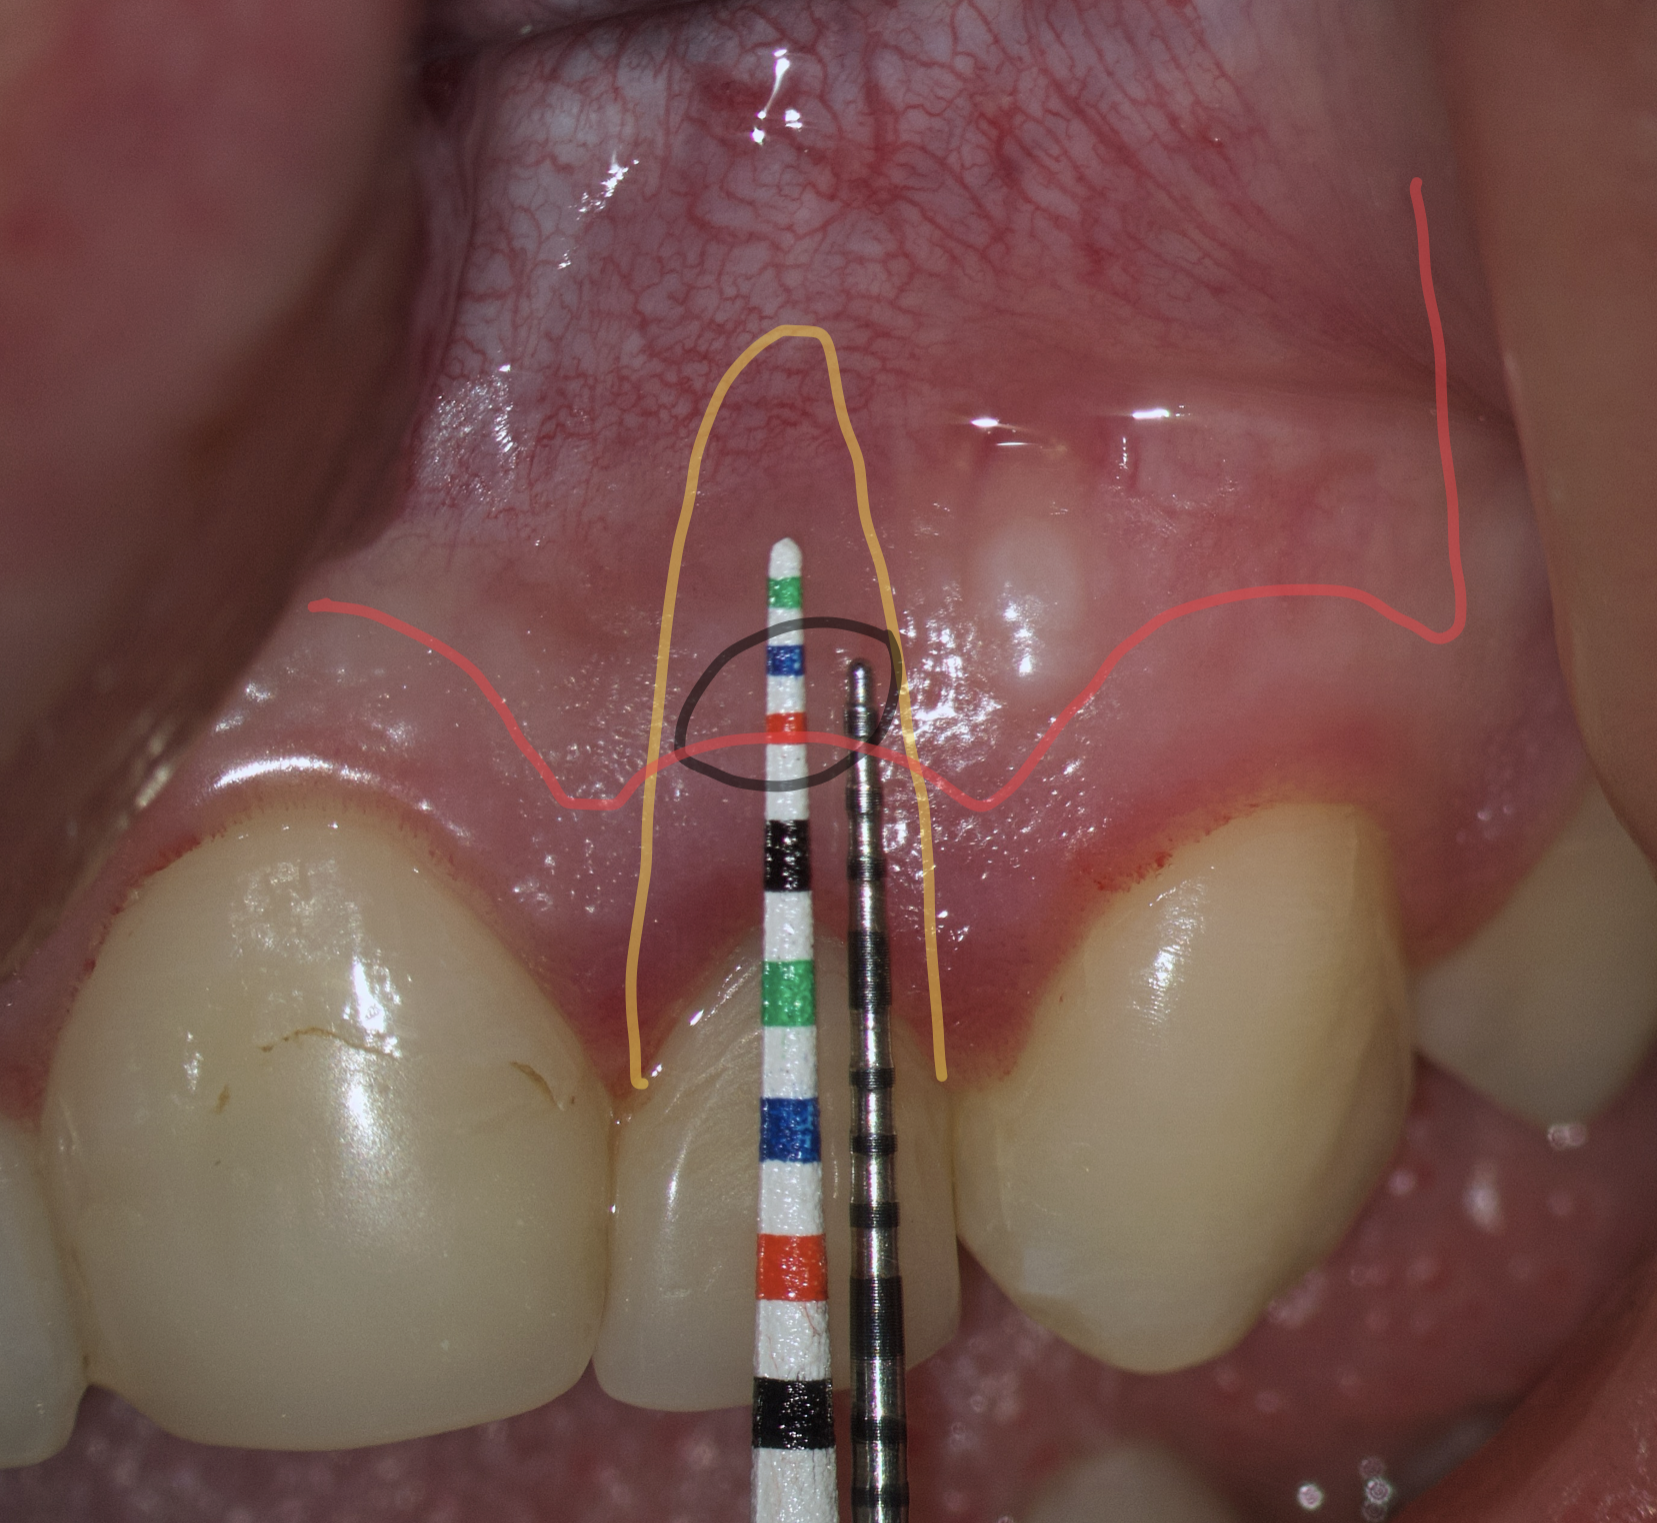

The most popular paramarginal or submarginal flap is the one designed by Clifford Ochsenbein and Raymond G. Luebke (1974) [4, 5]. The Ochsenbein-Luebke flap is formed by a scalloped horizontal sub-marginal incision placed within the attached gingiva, which follows roughly parallel to the contour of the gingival margin. The horizontal incision continues with two vertical releasing incisions [6]. These vertical incisions extend from a point 1 to 2 mm short of entering the mucobuccal fold to a point on the attached gingiva approximately 3 to 5 mm above or below the marginal gingiva and the sulcus depth (Figs 1 and 2) [7, 8].

The submarginal flap is only to be used, when there is a broad zone of attached gingiva with a minimum of 2 mm [9]. The width of the attached gingiva is then calculated on the basis of the distance from the base of the sulcus to the linea girlandiformis (mucogingival junction) [6]. Consequently, the incision must be placed at least 2 mm from the depth of the gingival sulcus. Extensive periodontal probing should be done to establish the depth of the gingival sulcus before the incision is made [10]. Periodontal probing should be conducted not only around the causative tooth but also in the adjacent teeth.

Sometimes the frenulum of the upper lip is massive and for avoid its dissection, it is permissible to perform a submarginal flap with one vertical incision located more distally. It is worth recognizing that this approach is applied to a root with medium length on which microsurgery is performed (Figs 3 and 4).